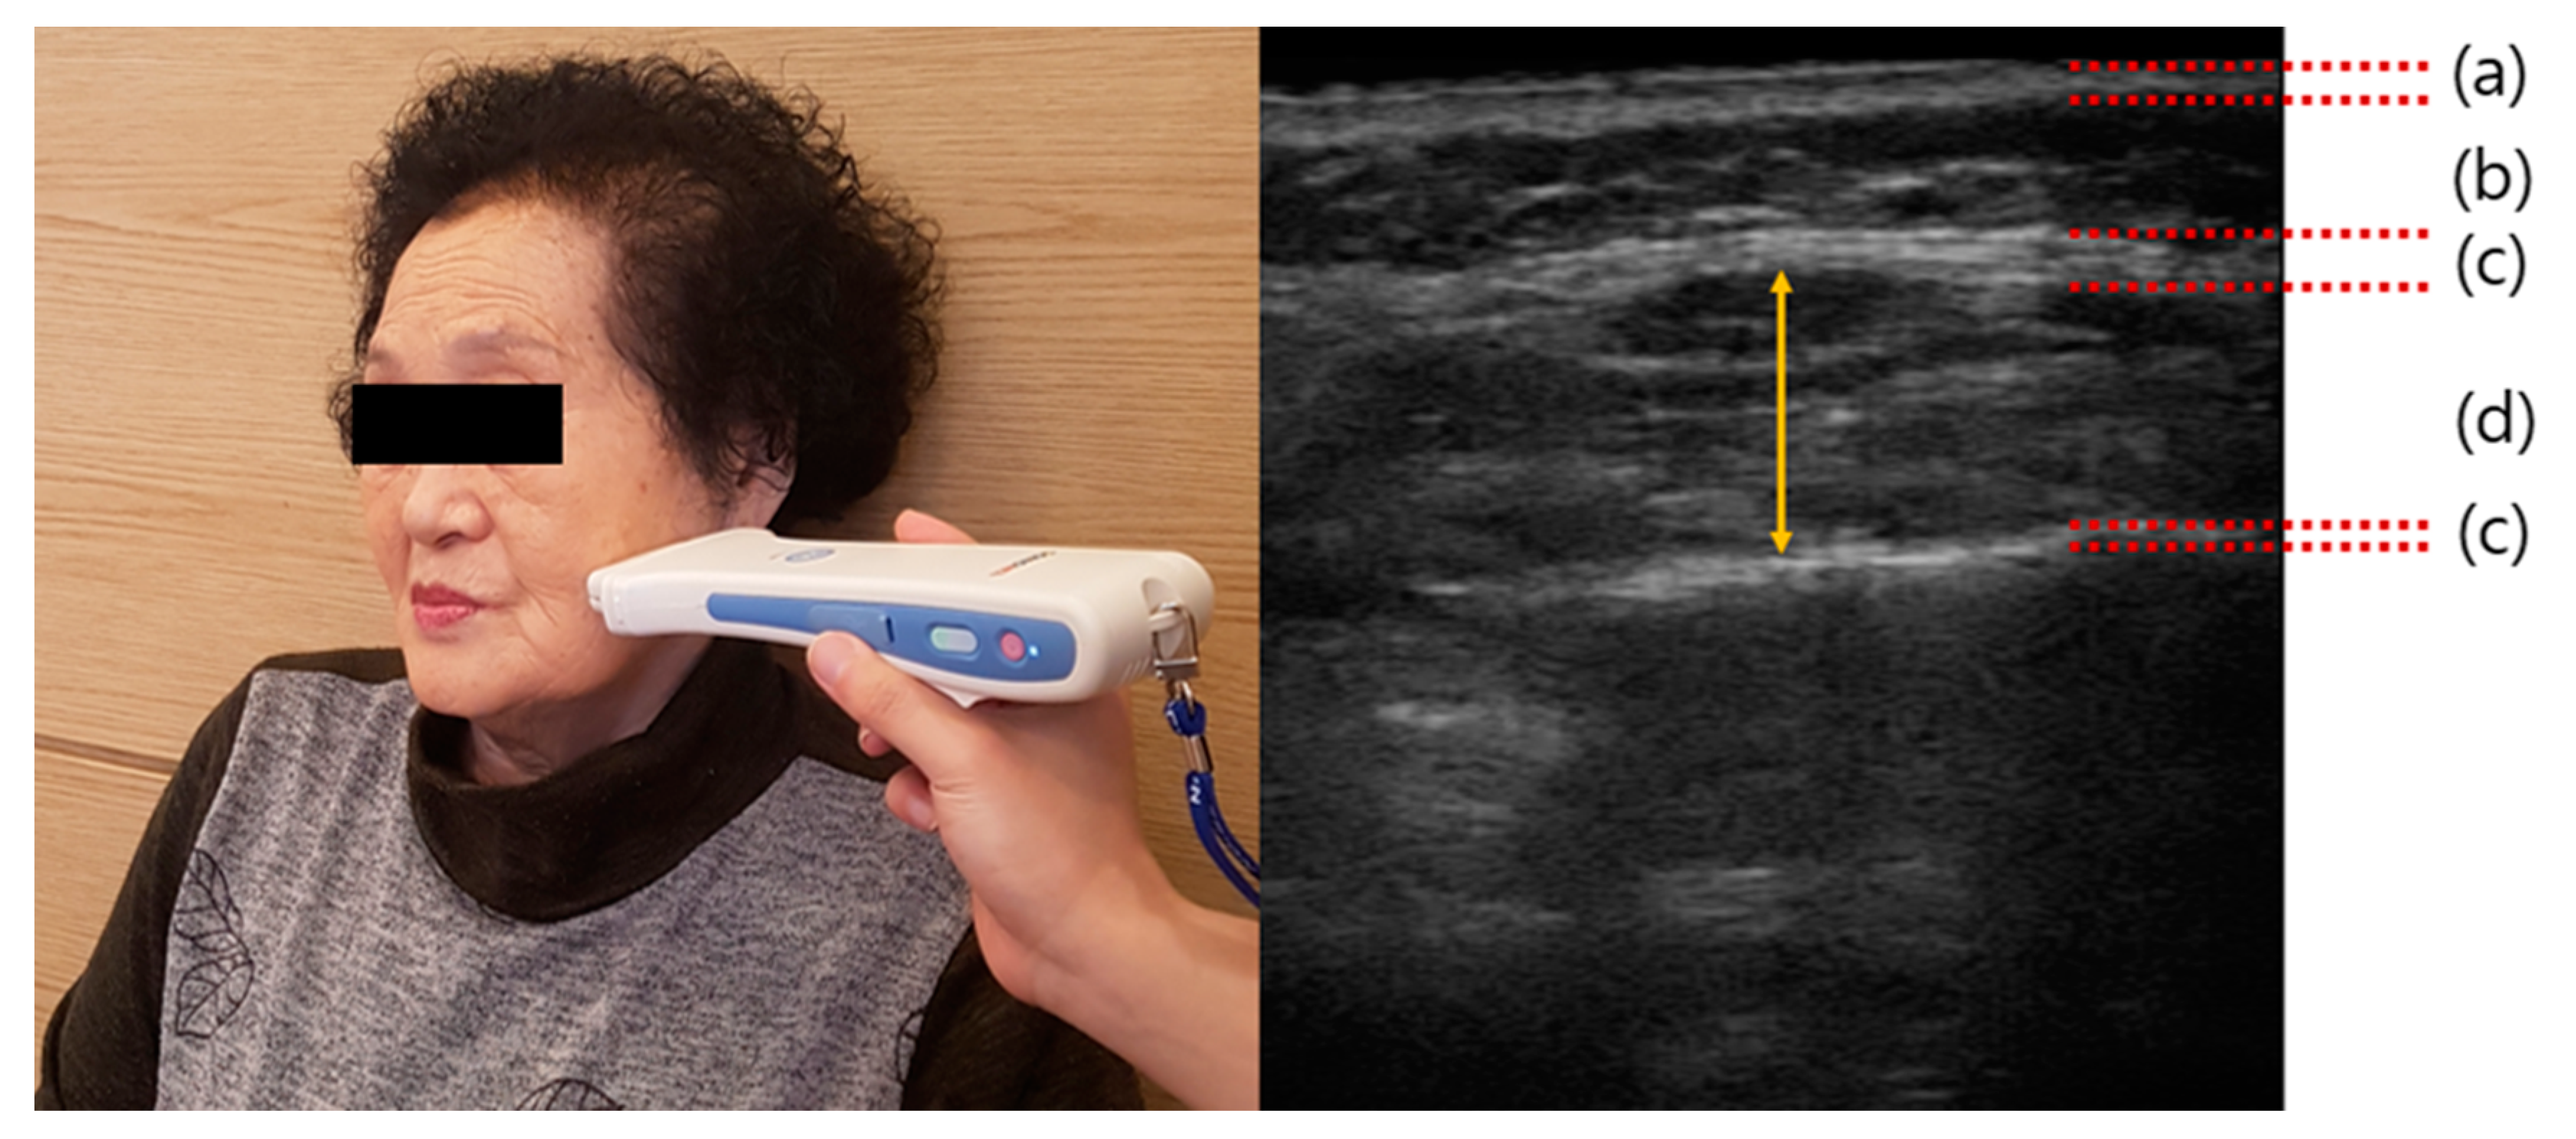

2.4. Outcome Measurement

- Yamaguchi, K.; Tohara, H.; Hara, K.; Nakane, A.; Yoshimi, K.; Nakagawa, K.; Minakuchi, S. Factors associated with masseter muscle quality assessed from ultrasonography in community-dwelling elderly individuals: A cross-sectional study. Arch. Gerontol. Geriatr. 2019, 82, 128–132. [Google Scholar] [CrossRef] [PubMed]